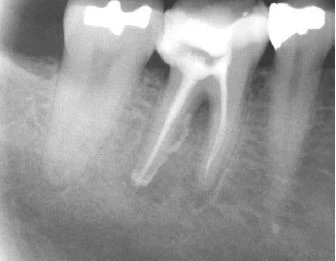

Thông thường khi một răng chết tuỷ thì hình ảnh X quang của nó sẽ thay đổi, mất xương xảy ra ở vùng chóp. Tuy nhiên, khi một răng bị nứt dọc hoặc chia chân răng, vùng mất xương có khuynh hướng cho hình ảnh “vòng sáng”, thấu quang xung quanh chân răng. Vùng thấu quang cũng có thể đi dọc toàn bộ một bên chân răng và thường được gọi là tổn thương “dạng chữ J”.

Hình 13. Hình ảnh tiêu xương “dạng chữ J”